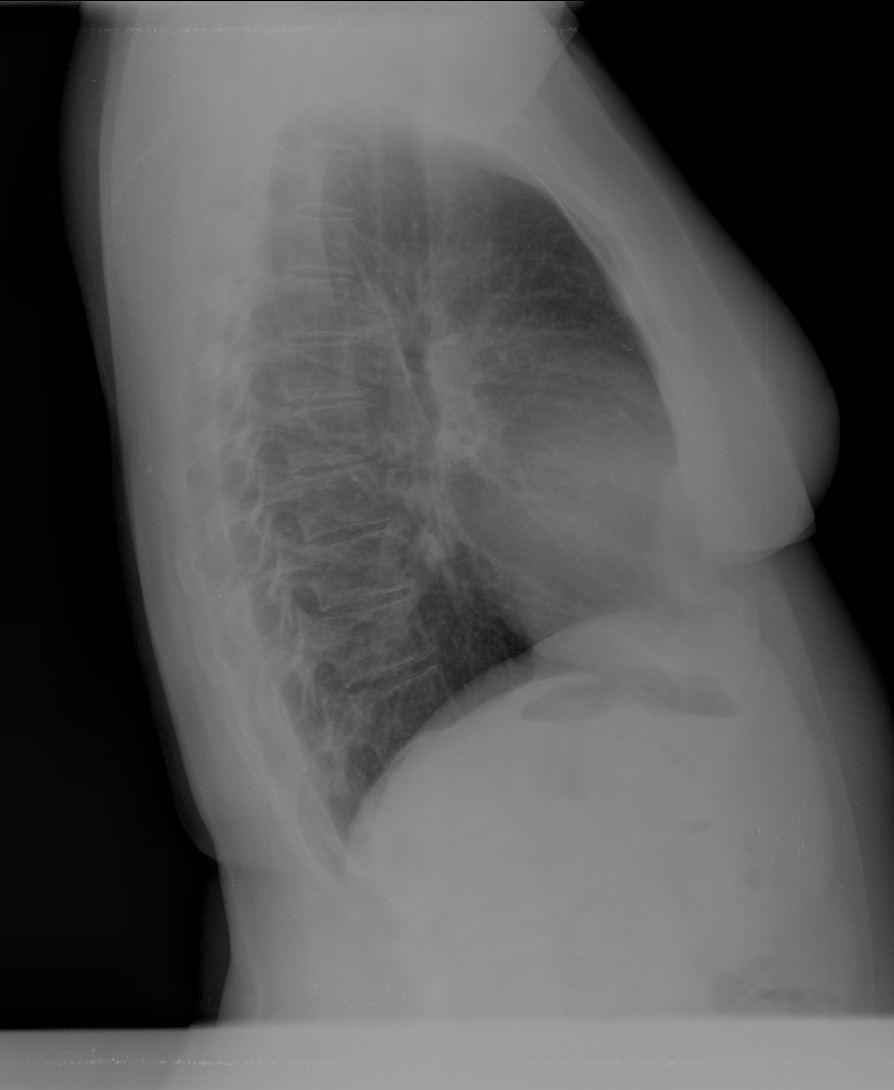

CASO: Febrícula y tos de 4 días de evolución.

Hallazgos:

- En la placa PA se observa una asimetría en los hilios pulmonares, el hilio izquierdo tiene una densidad aumentada.

- Tras examinar la placa lateral se observa un aumento de densidad en la columna que puede ser compatible con una condensación, es el signo de la desnificación vertebral.

SIGNO DE LA DENSIFICACIÓN VERTEBRAL: En la radiografía lateral normal, la densidad de la columna torácica tiende a disminuir desde la parte superior hasta el diafragma; la alteración de ese patrón por la presencia de una densidad superpuesta a la columna, indica la existencia de una consolidación pulmonar. Este signo adquiere especial valor cuando en la proyección posteroanterior la consolidación está oculta en el espacio retrocardíaco o en la base pulmonar.